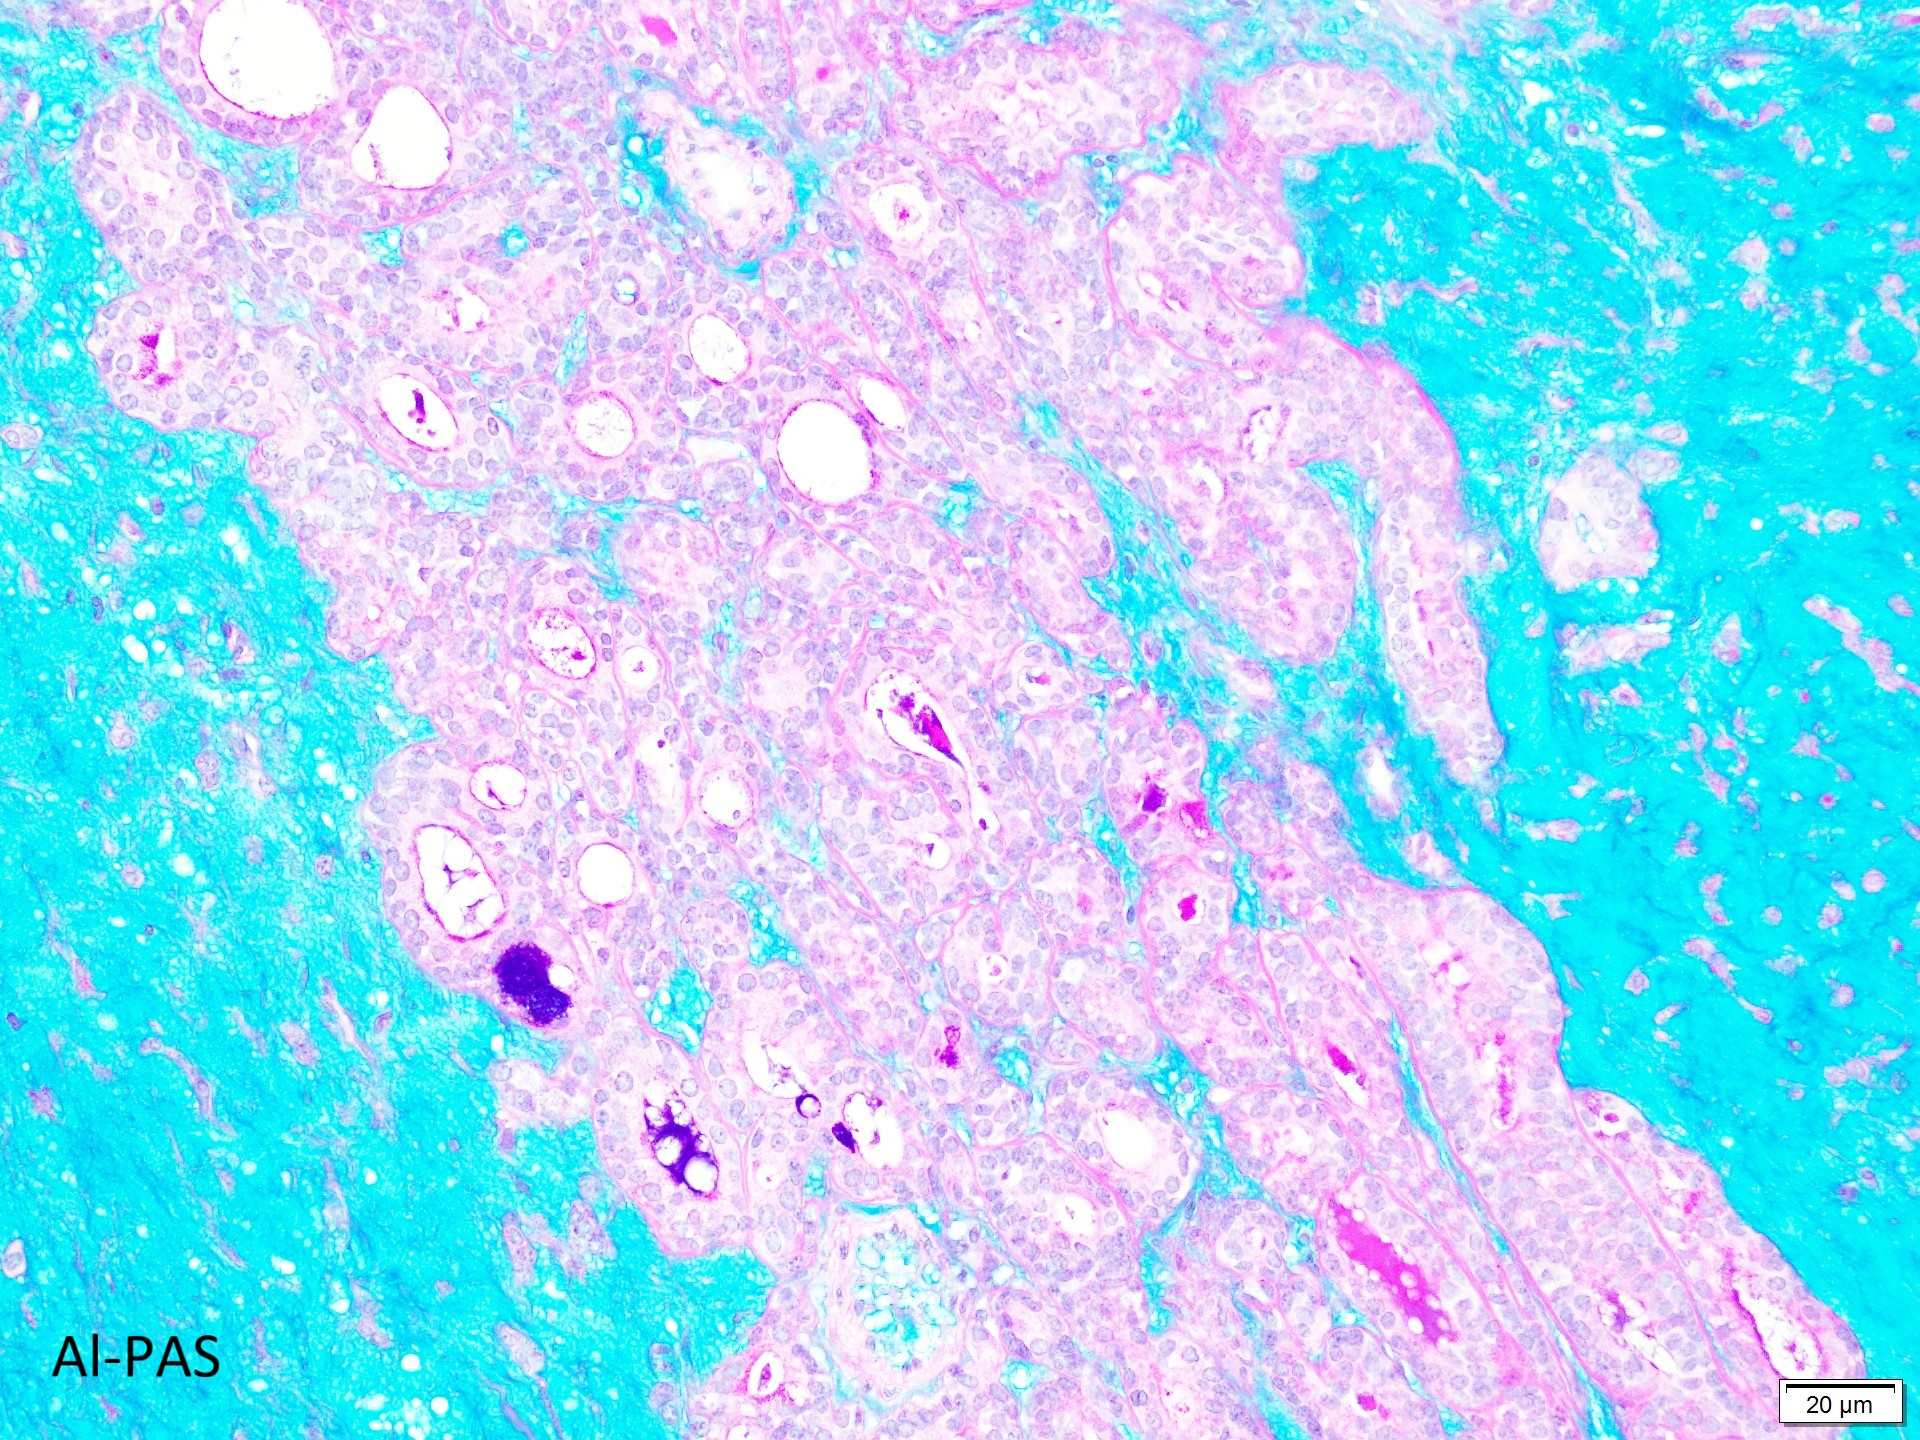

Giemsa染色で異染性を示す間質粘液と、円形〜紡錘形の筋上皮細胞、円〜類円形の核で均一な大きさの結合性良好な上皮細胞集塊がみられる。

組織標本では、豊富な粘液腫状基質に、星芒状・短紡錘形の筋上皮細胞成分と、管状を示す腺管上皮成分を認める。